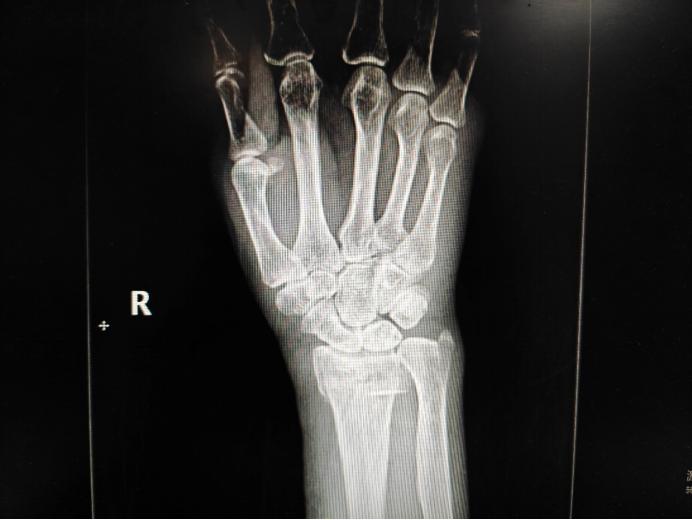

此次手术为女性患者,89岁,入院前1日因跌倒导致右股骨粗隆间骨折合并右桡骨远端粉碎性骨折,症状为右下肢及右腕关节肿胀、畸形伴活动受限,严重影响日常生活,保守治疗卧床时间长且效果不佳。患者既往身体较差,患有冠状动脉粥样硬化性心脏病、心律失常(房性早搏合并室性早搏)、高血压(2级,极高危)、脑梗死后遗症,患者前往多家医院诊治,均因患者的全身情况对于手术是一个巨大挑战而被婉拒。

患者股骨粗隆间骨折